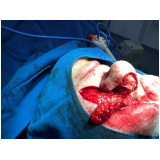

Conheça os procedimentos de excelência para a realização de uma cirurgia plástica a laser!